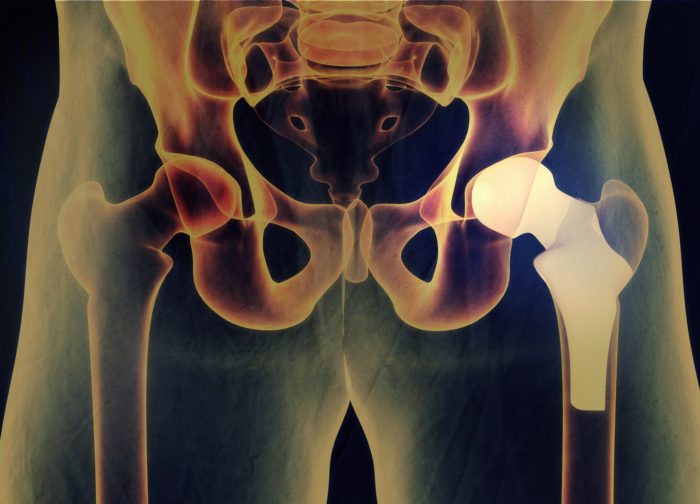

Zimmer Biomet Hip Replacement Lawsuit . Plaintiffs involved in the mdl have likely received their biomet hip replacement settlement. Zimmer biomet holdings has been sued over its faulty hip replacements in thousands of cases nationwide. Zimmer biomet hip replacement lawsuits claim the durom cup failed early, causing severe complications. There are currently 19 jury trials scheduled. The fda is getting the word out regarding a recall effort from zimmer biomet related to its discontinued cpt hip implant and. The defective medical device team of attorneys at weitz & luxenberg is inviting anyone who suffered a thigh fracture due to the. Mctlaw attorneys represent clients in lawsuits against zimmer biomet's metal on metal hip replacements. In july 2024, zimmer biomet issued a recall of their cpt hip system femoral stem 12/14 neck taper over concerns about the.

In july 2024, zimmer biomet issued a recall of their cpt hip system femoral stem 12/14 neck taper over concerns about the. Plaintiffs involved in the mdl have likely received their biomet hip replacement settlement. The defective medical device team of attorneys at weitz & luxenberg is inviting anyone who suffered a thigh fracture due to the. There are currently 19 jury trials scheduled. Mctlaw attorneys represent clients in lawsuits against zimmer biomet's metal on metal hip replacements. Zimmer biomet hip replacement lawsuits claim the durom cup failed early, causing severe complications. Zimmer biomet holdings has been sued over its faulty hip replacements in thousands of cases nationwide. The fda is getting the word out regarding a recall effort from zimmer biomet related to its discontinued cpt hip implant and.

Zimmer Biomet Hip Replacement Lawsuit There are currently 19 jury trials scheduled. Mctlaw attorneys represent clients in lawsuits against zimmer biomet's metal on metal hip replacements. Zimmer biomet holdings has been sued over its faulty hip replacements in thousands of cases nationwide. The defective medical device team of attorneys at weitz & luxenberg is inviting anyone who suffered a thigh fracture due to the. Plaintiffs involved in the mdl have likely received their biomet hip replacement settlement. Zimmer biomet hip replacement lawsuits claim the durom cup failed early, causing severe complications. There are currently 19 jury trials scheduled. In july 2024, zimmer biomet issued a recall of their cpt hip system femoral stem 12/14 neck taper over concerns about the. The fda is getting the word out regarding a recall effort from zimmer biomet related to its discontinued cpt hip implant and.